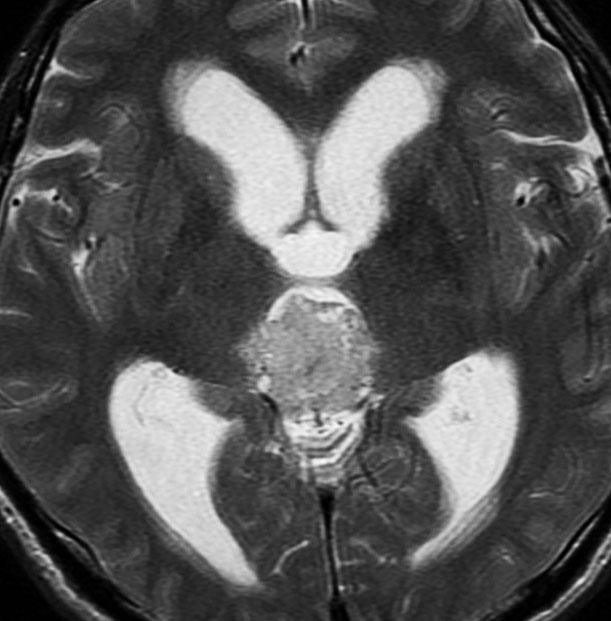

成人男性の松果体芽腫です。左のCTでは白く見える石灰化があります。水頭症があって頭痛と嘔吐で発症しました。右のMRIでは腫瘍の形が丸くなくて周囲の脳に浸潤したり脳室の壁などにべっとり広がっているように見えます。悪性腫瘍の特徴的な像で,開頭手術をしても摘出できないことが判ります。松果体芽腫は悪性度が高くて(WHOグレード4),脊髄などに播種転移したりしますし,手術だけでは治りません。

腫瘍は定位脳手術で生検をしました。水頭症に対しては内視鏡で第3脳室開窓術を行なって症状を改善しました。左のMRIで水頭症が良くなっているのが判ると思います。それから,全脳脊髄に30グレイの放射線治療をして腫瘍局所には24グレイの照射を追加しました。同時にICE化学療法というのを6コースしました。右のMRIでは治療が終わって小さく固まった残存腫瘍が見えます。この残存腫瘍は第3脳室の壁にくっついていて摘出するリスクがとても高いと思いましたので,そのままずーっと10年間様子を見ていますが再発していません。でも,残存腫瘍がなんとか取れる時は徹底的に取ってしまった方が再発率は少ないといえます。